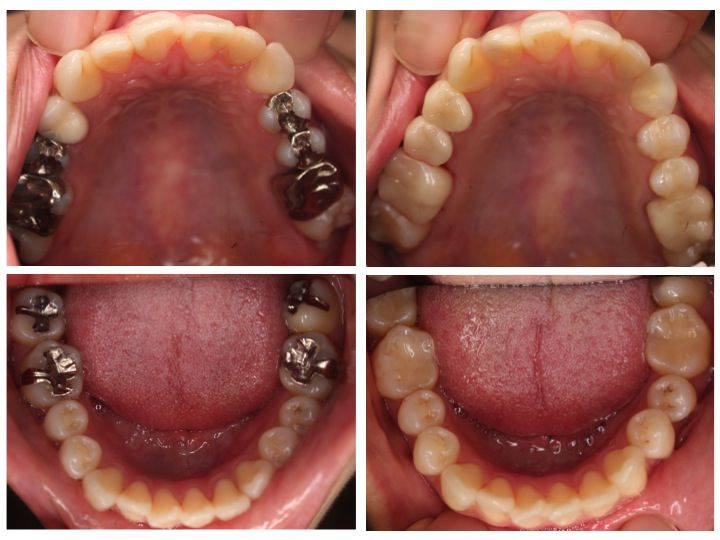

最後に臨床例をみてみましょう。

左側が初診時で右側が治療後です。

このように口腔内全ての金属の除去を希望されて来院される患者様は

非常に多いです。

毎日のようにオールセラミック治療を行っています。

上顎は全てオールセラミックで治療を行っていますが、

下顎は保険診療でレジンという素材で治療を行っています。

部分的な小さな詰め物は、保険診療でも十分治療可能です。